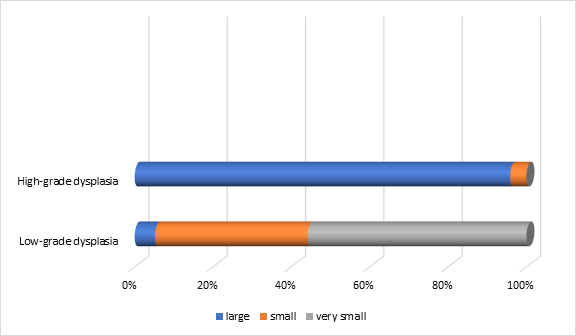

The distribution of polyps varied statistically significantly (p=0.0001) in relation to the size and dysplasia of the premalignant lesions. The smallest size was recorded in polyps with low-grade dysplasia (n=153), while large sizes were more commonly found in those with high-grade dysplasia (n=23). This demonstrates a direct relationship between size and dysplasia, with 74.2% of polyps with high dysplasia being classified as large (Figure 7).

|

Fig. 7 Distribution of polyps in relation to size and their degree of dysplasia in the patients included in the study Note: size of the polyps – large, small, very small |